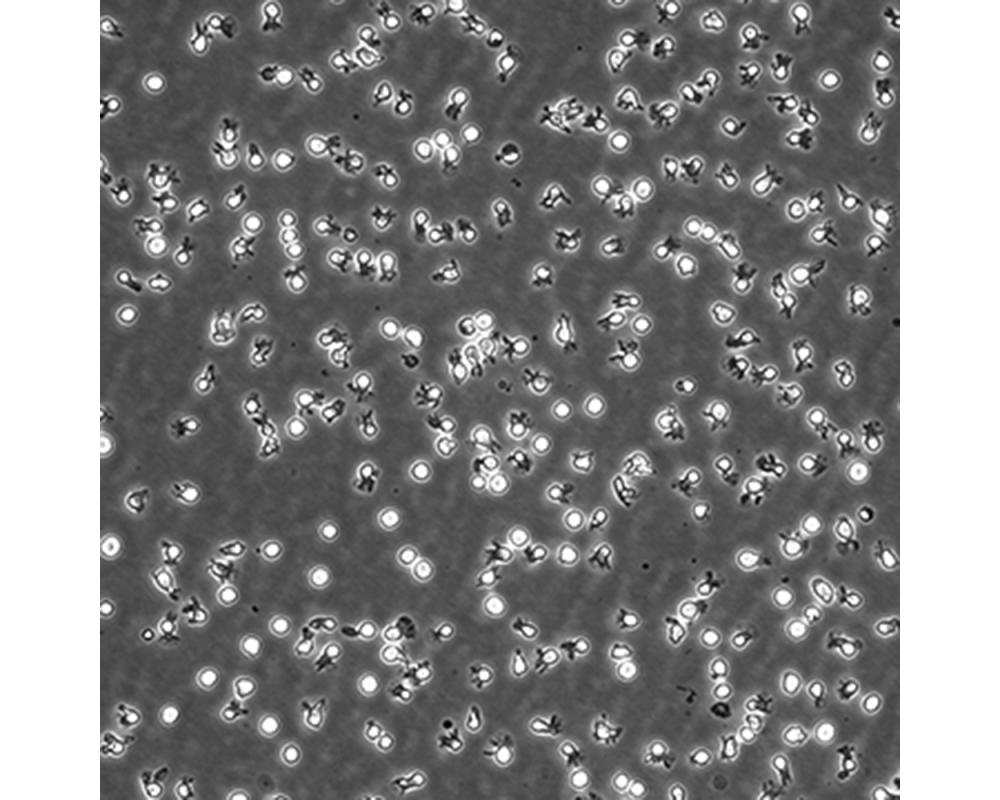

中文名稱 人彌漫大B細胞淋巴瘤細胞

組織來源 彌漫大B細胞淋巴瘤;男性

生長特性 懸浮

培養基 IMDM,90%;FBS,10%;雙抗。

傳代方法 Maintain cultures at a cell concentraion between between 1 X 10(5) and 1 X 10(6) viable cells/ml.

培養條件 Atmosphere: Air, 95%; CO2, 5%。Temperature: 37℃